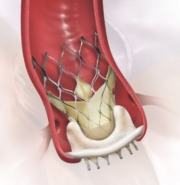

TAVIは、カテーテルに装填された人工弁を、狭窄して機能不全におちいった自己弁の上に拡張し留置します。当院では、風船拡張の手法で留置する人工弁1種類と形状記憶の特性を生かした自己拡張能を有する人工弁の2種類を用いています。鼡径部の大腿動脈から挿入する経大腿動脈アプローチ法、胸の皮膚の小さな切開から心臓の先の心尖部の動きの少ない部位に挿入する経心尖部アプローチ法、他に鎖骨下動脈や胸部大動脈を経由したアプローチ法が、事前にえられた画像情報により、ハートチームにおける検討のもと、適正に選択されます。

TAVIは、カテーテルに装填された人工弁を、狭窄して機能不全におちいった自己弁の上に拡張し留置します。当院では、風船拡張の手法で留置する人工弁1種類と形状記憶の特性を生かした自己拡張能を有する人工弁の2種類を用いています。鼡径部の大腿動脈から挿入する経大腿動脈アプローチ法、胸の皮膚の小さな切開から心臓の先の心尖部の動きの少ない部位に挿入する経心尖部アプローチ法、他に鎖骨下動脈や胸部大動脈を経由したアプローチ法が、事前にえられた画像情報により、ハートチームにおける検討のもと、適正に選択されます。

生体弁を小さく折りたたみ収納したカテーテルを大動脈まで送り込み、すでに植え込まれている外科生体弁の内側で新しい生体弁をゆっくりと展開させ留置します。